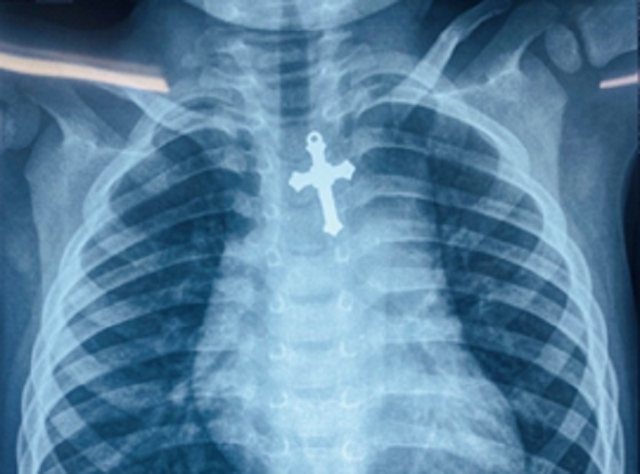

| Cây thánh giá kẹt ở thực quản, nguy cơ xuyên vào trung thất đe dọa trực tiếp đến tính mạng bệnh nhi. (Ảnh: Gia đình) |

Các bác sĩ đã tiến hành hội chẩn nhanh và xác định, đây là một trường hợp dị vật thực quản phức tạp, nguy hiểm. Cây thánh giá có hình dáng góc cạnh, sắc nguy cơ gây tổn thương thành thực quản, xuyên thủng vào trung thất, tổn thương các mạch máu và các cơ quan lân cận đe dọa trực tiếp đến tính mạng bệnh nhi. Các bác sĩ quyết định thực hiện phương pháp gây mê và nội soi gắp dị vật.

Sau hơn 45 phút trong phòng nội soi các bác sĩ đã gắp thành công cây thánh giá ra ngoài qua đường miệng giúp bệnh nhi vượt qua cơn nguy kịch. Kiểm tra sau nội soi ghi nhận, lòng thực quản bệnh nhi có vài điểm trầy xước, sung huyết nhưng may mắn không thủng và không có tai biến, biến chứng nguy hiểm xảy ra.